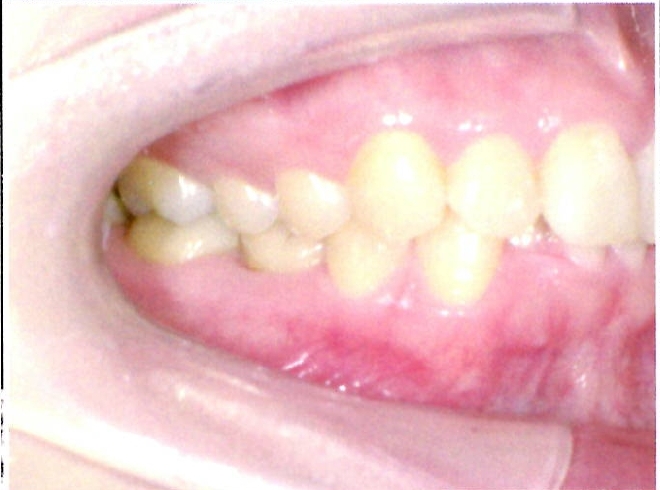

| 主訴・治療前の状態 | 前歯が噛み合っていない状態(開咬傾向)で、犬歯がやや前方に突出しており、見た目にお悩みがありました。 |

| 治療内容 | 上下左右の第一小臼歯(4番)計4本を抜歯し、そのスペースを利用して歯列を整え、前歯の噛み合わせを改善しました。 |

| 治療結果 | 前歯がしっかり噛み合うようになり、見た目も美しく整いました。患者様の満足度が非常に高かった症例です。 |